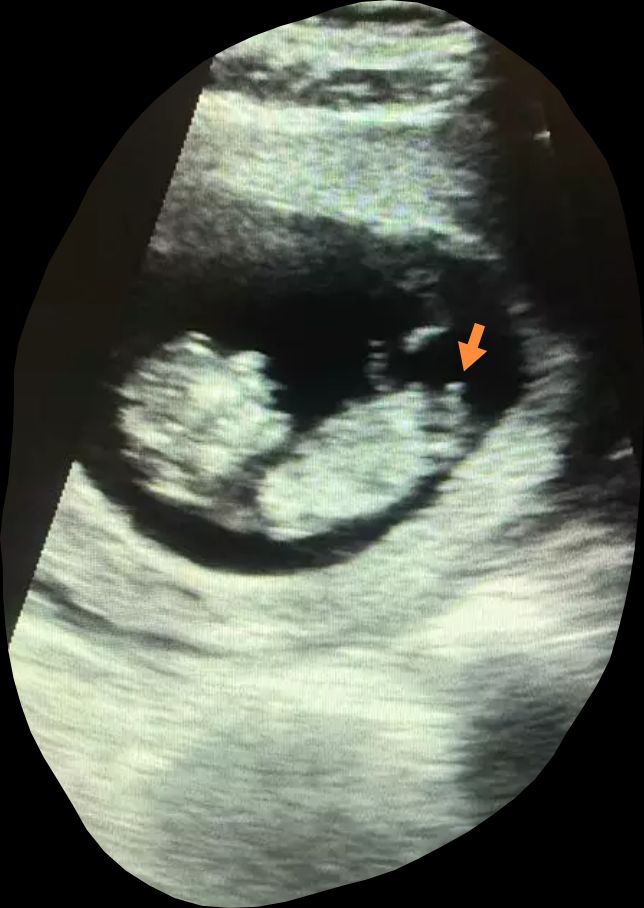

Половой бугорок

Алёна Хаустова, Изображение вот половой бугорок торчащий вверх)

Кристина, сказала, что похож на мальчика, но я не могу понять, где там половой бугорок 😵‍💫

Мила Милова, торчит в конце туловища вверх )

Кристина, я думала, это пуповина😂